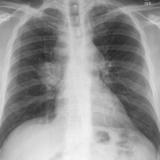

Lung Cancer

Nodules & Masses

Album: Nodules & Masses